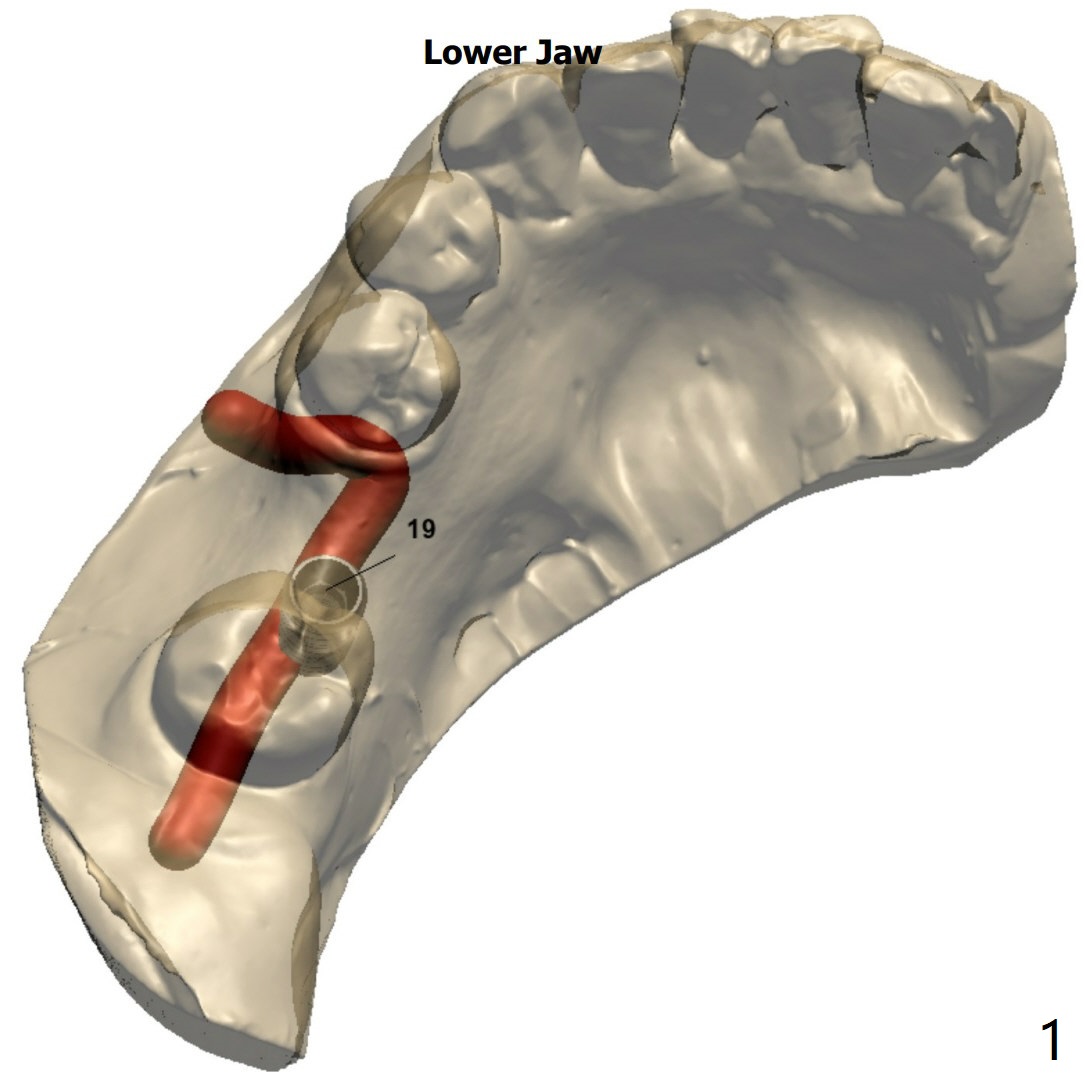

Distal Placement of Narrow Implant for Upright

A 57-year-old woman agrees to orthodontically upright #18 associated with #19 implant placement after #12 implant placement.